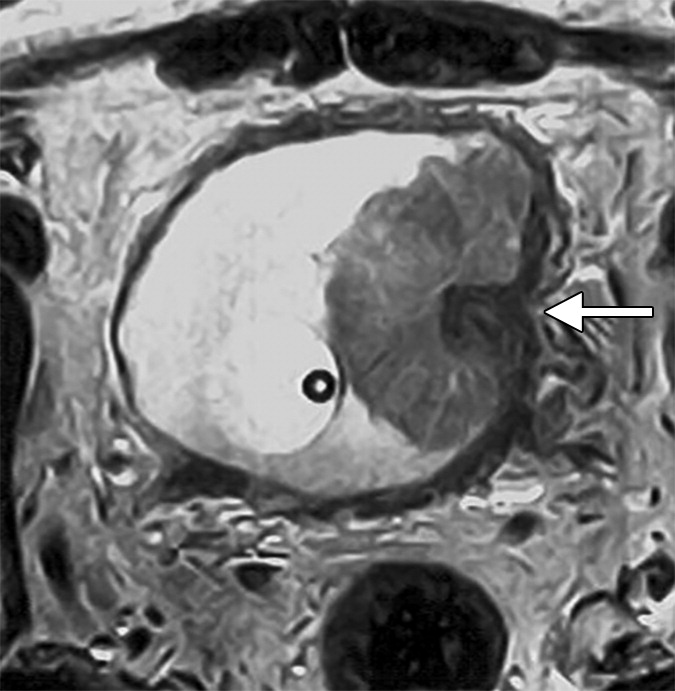

Рак мочевого пузыря — злокачественная опухоль, развивающаяся из клеток слизистой оболочки. На ранних стадиях может протекать бессимптомно, по мере прогрессирования проявляется кровью в моче, болью и нарушением мочеиспускания. Патологический процесс может распространяться на другие органы или прорастать в стенку.

Полипы и доброкачественные опухоли. Новообразования часто дают о себе знать лишь тогда, когда достигают крупных размеров и нарушают работу мочеполовой системы, МРТ позволяет обнаружить их на ранних стадиях.

Метастазы и поражение лимфоузлов — вторичные опухолевые очаги, которые появляются при распространении рака из других органов (например, простаты, матки, кишечника) в мочевой пузырь или лимфоузлы.